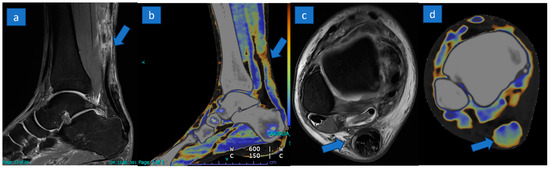

Identification of Achille’s Tendon Tears: Diagnostic Accuracy of Dual-Energy CT with Respect to MRI

3.3. DECT Results